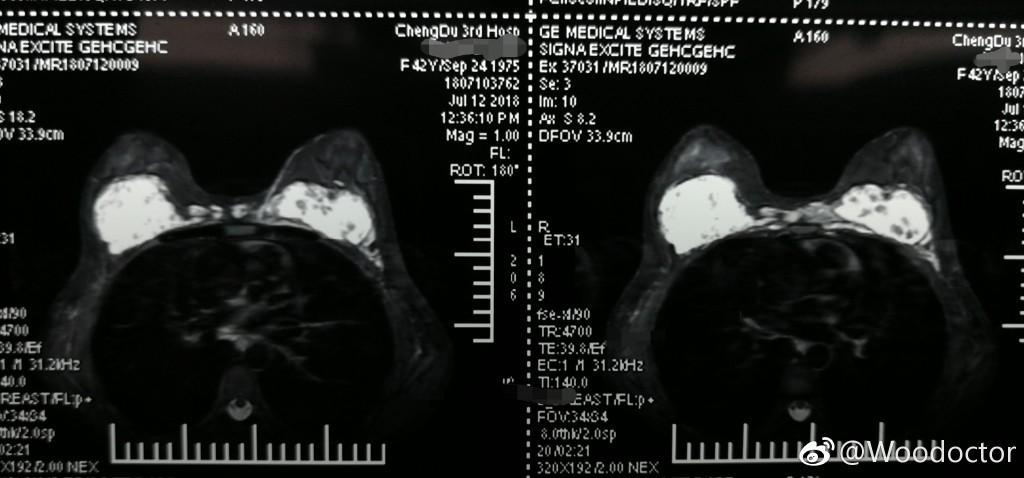

張女士注射的隆胸材料已轉(zhuǎn)移至兩胸之間